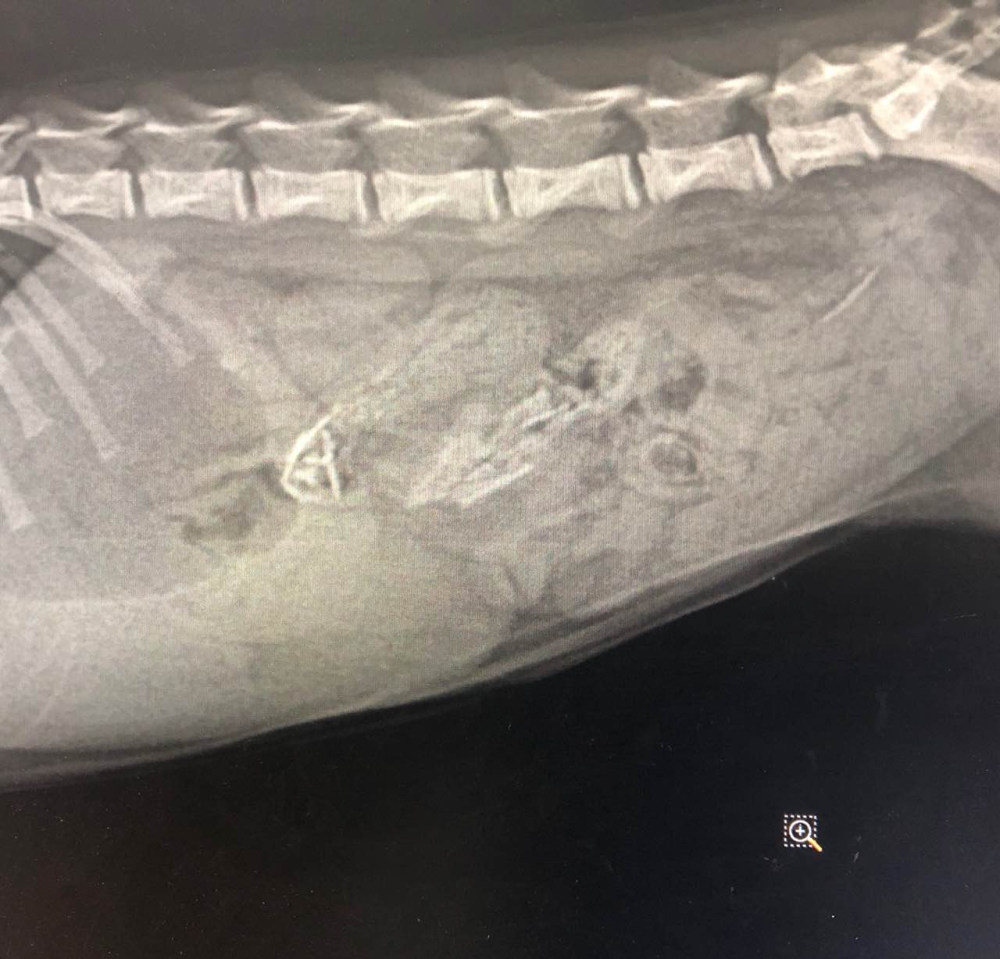

2023-06-06 日常问答 3 评论 169 喜欢 分享 体验版小友 💙🤖 这个人很懒,还没有简介 查看TA的全部内容 +关注 宠也 去发现更多有趣内容 微信扫码打开宠也小程序 体验更多「宠也」新功能 评论 3 operationcc 2023-06-06 55 排不出来最好迟早手术 逸久久 2023-06-06 57 主要看这个是什么吧?这个图片也看不清楚,我家之前是棉絮吃到肚子里结团了。灌了几天什么粉还是药水就排出来了。不然就得做手术,医生说前面两天最重要,两天还没排出就得做手术了。 所欲所求 2023-06-06 85 如果你要做手术,建议找个靠谱的医院吧,小猫体型什么都小,手术的难度会增加,熟练的医生成功率会高一些。 我也来讲两句

排不出来最好迟早手术